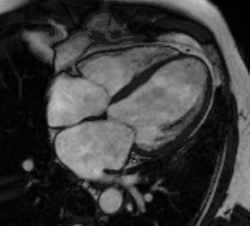

Partial Anomalous Pulmonary Venous Drainage by CMR